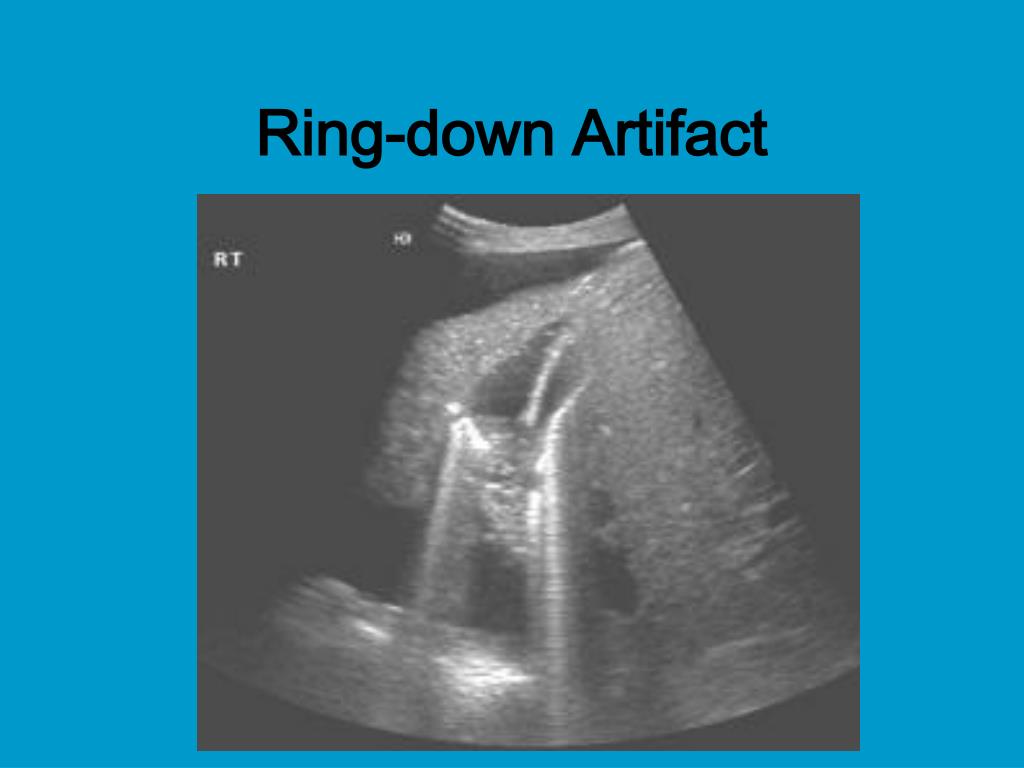

17. Ring-down Artifact - is another type of reverberation that is produced by small gas bubbles, such as air & appear as a single, long, strong echo behind the reflector

18. Ring-down Artifact

19. Ring-down Artifact